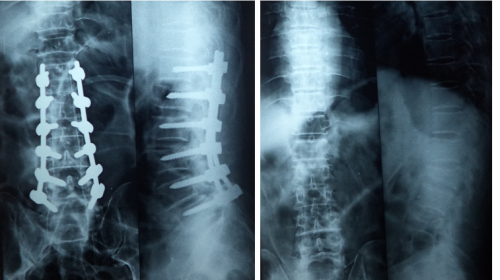

Spinal surgeries

The vertebral column and the vertebrae give shape to the body. They give the height to the body and maintain the erect position. They help us to bend forwards, to turn to sides and to bend backwards. This vertebral column gives protection to the spinal cord and nerves which travel from the base of the brain to the tip of the vertebral column. Vertebral fractures occur due to the fall from height. They can be injured during the time of accidents.